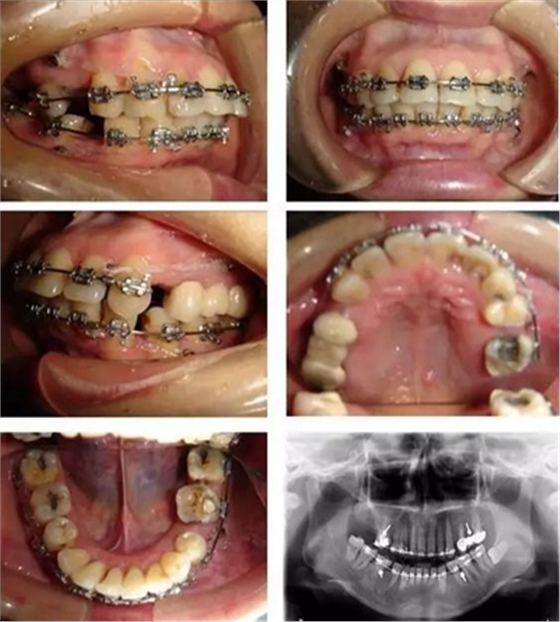

▲ 圖3 矯治中,利用微種植體支抗內(nèi)收前牙時的牙(牙合)像及曲面斷層片